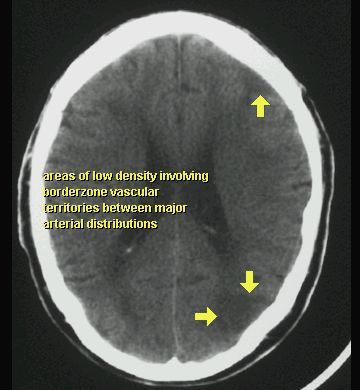

UDAR NIEDOKRWIENNY MÓZGU (ZAWAŁ MÓZGU)

TK